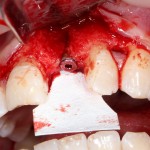

Если после этого BioGide намочить физраствором, им легко укрыть получившийся объем:

Для надежности можно зафиксировать пинами:

Ну и, швы: